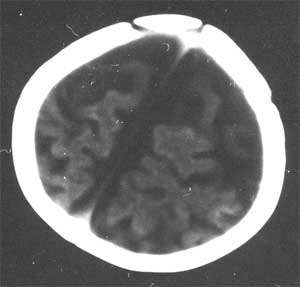

通过脑ct看医生说比较严重 ct检查报告是:右侧基底节区低密度灶,脑沟裂明显增宽,脑室系统清度扩大,中线结构无移位。 ct诊断:1。右侧基底节区缺血性改变 2。脑发育不良

幕上幕下脑室、脑池、脑沟均见扩张积液,考虑脑发育不良。片子质量不好,前囟门似乎偏小,颅骨骨缝不知是否有闭合。9个月幼儿,头围应该不小于40厘米,请测量头围周径。应该没有胼胝体发育不良。至于“右侧基底节区缺血性改变”,片子质量差,看不清楚。

从ct片看1大脑纵裂增宽2侧脑室扩大3蛛网膜下腔增宽 应考虑1胼胝体发育不良,2脑发育不良或萎缩(两周前一般无临床意义应称蛛网膜下腔增宽或外周性脑积水)

粗看:1。双侧额颞顶叶均有不同程度萎缩,脑实质变薄,2。脑室系统对称性扩张,大脑沟裂增宽变深。3。双基底节区未见明确低密灶,胼胝体发育良好。综上所述考虑有:1)大脑发育不良;2)严重脑缺血缺氧性脑病后遗症?个人意见仅供参考。